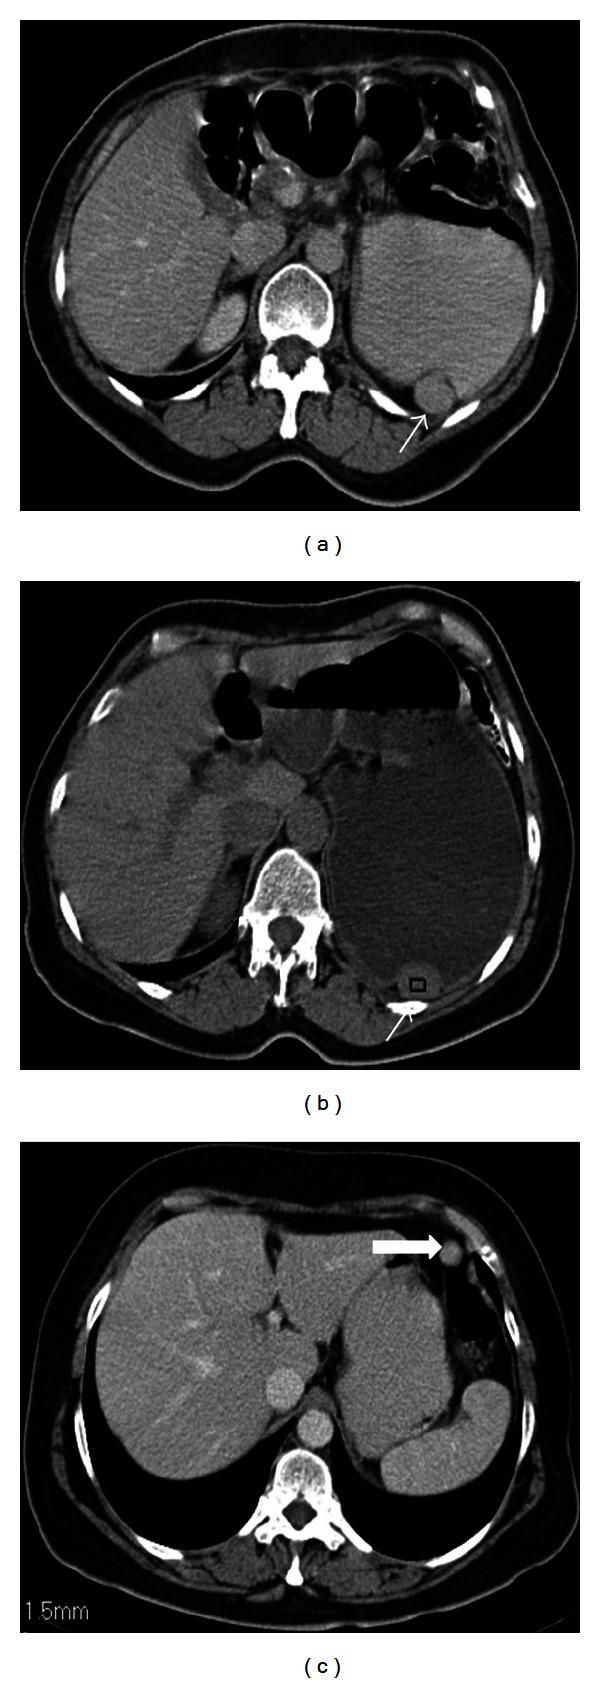

脾脏在形状、大小和位置上的异常:图文综述

Splenic anomalies of shape, size, and location: pictorial essay.

Spleen can have a wide range of anomalies including its shape, location, number, and size. Although most of these anomalies are congenital, there are also acquired types. Congenital anomalies affecting the shape of spleen are lobulations, notches, and clefts; the fusion and location anomalies of spleen are accessory spleen, splenopancreatic fusion, and wandering spleen; polysplenia can be associated with a syndrome. Splenosis and small spleen are acquired anomalies which are caused by trauma and sickle cell disease, respectively. These anomalies can be detected easily by using different imaging modalities including ultrasonography, computed tomography, magnetic resonance imaging, and also Tc-99m scintigraphy. In this pictorial essay, we review the imaging findings of these anomalies which can cause diagnostic pitfalls and be interpreted as pathologic processes.

摘要

脾脏可出现多种异常,包括其形状、位置、数量和大小。虽然这些异常大多是先天性的,但也有后天性类型。影响脾脏形状的先天性异常有分叶、切迹和裂隙;脾脏的融合和位置异常有副脾、脾胰融合和游走脾;多脾可与一种综合征相关。脾组织植入和小脾脏是分别由创伤和镰状细胞病引起的后天性异常。通过使用不同的成像方式,包括超声、计算机断层扫描、磁共振成像以及锝-99m闪烁扫描,这些异常很容易被检测到。在这篇图文文章中,我们回顾了这些异常的影像学表现,它们可能导致诊断陷阱,并被解释为病理过程。